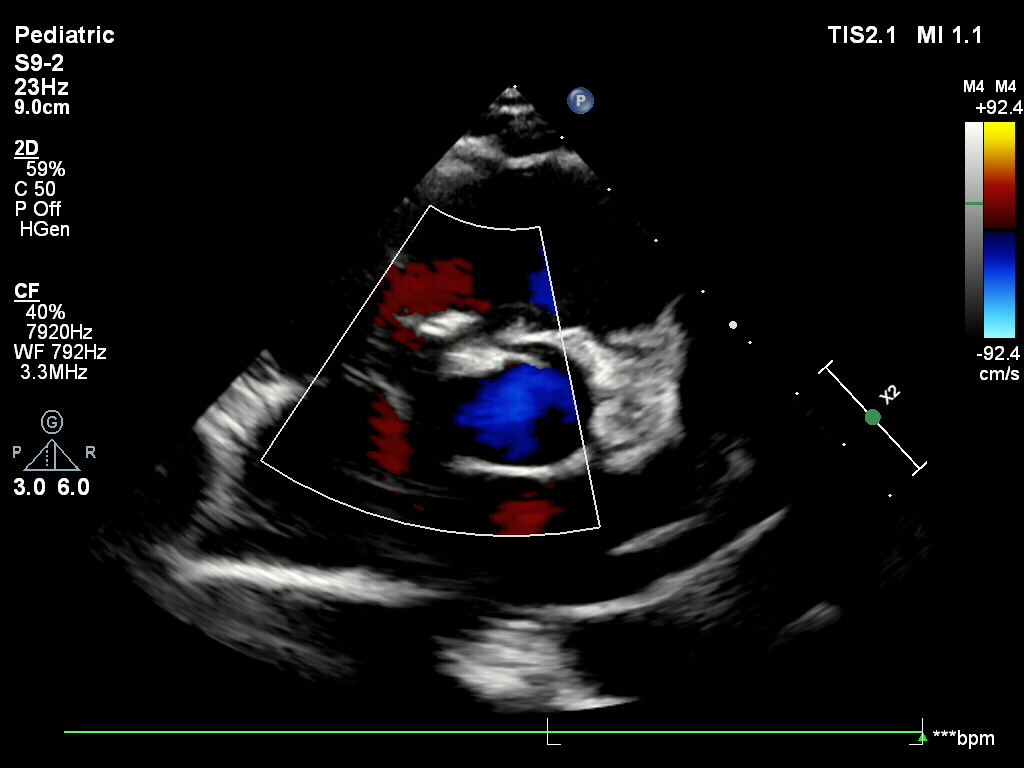

超声下可见右盘面展开

超声下确认封堵器位置正确

骑跨于室间隔两侧

封堵器的两个伞面与室间隔平行

释放封堵器后,超声下观察封堵器形态良好

无残余分流,封堵成功